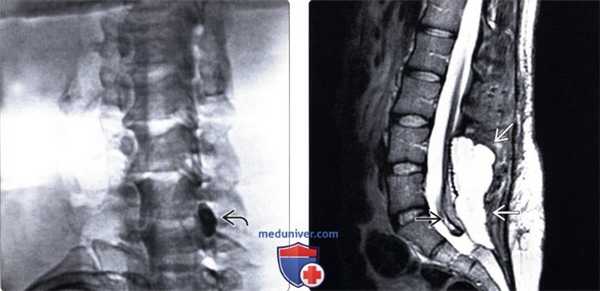

(Слева) Т2-ВИ, сагиттальная проекция: у молодой женщины, отмечающей выраженную головную после люмбальной пункции, определяются признаки накопления жидкости в дорзальной части эпидурального пространства связанное с истечением ликвора через постпункционный дефект.

(Справа) Нa аксиальном Т2-ВИ другого пациента визуализируется крупная заполненная жидкостью полость в паравертебральных тканях поясничной области, распространяющаяся из гемиляминэктомического дефекта справа в подкожную клетчатку. Дуральный мешок при этом не смещен и не деформирован.